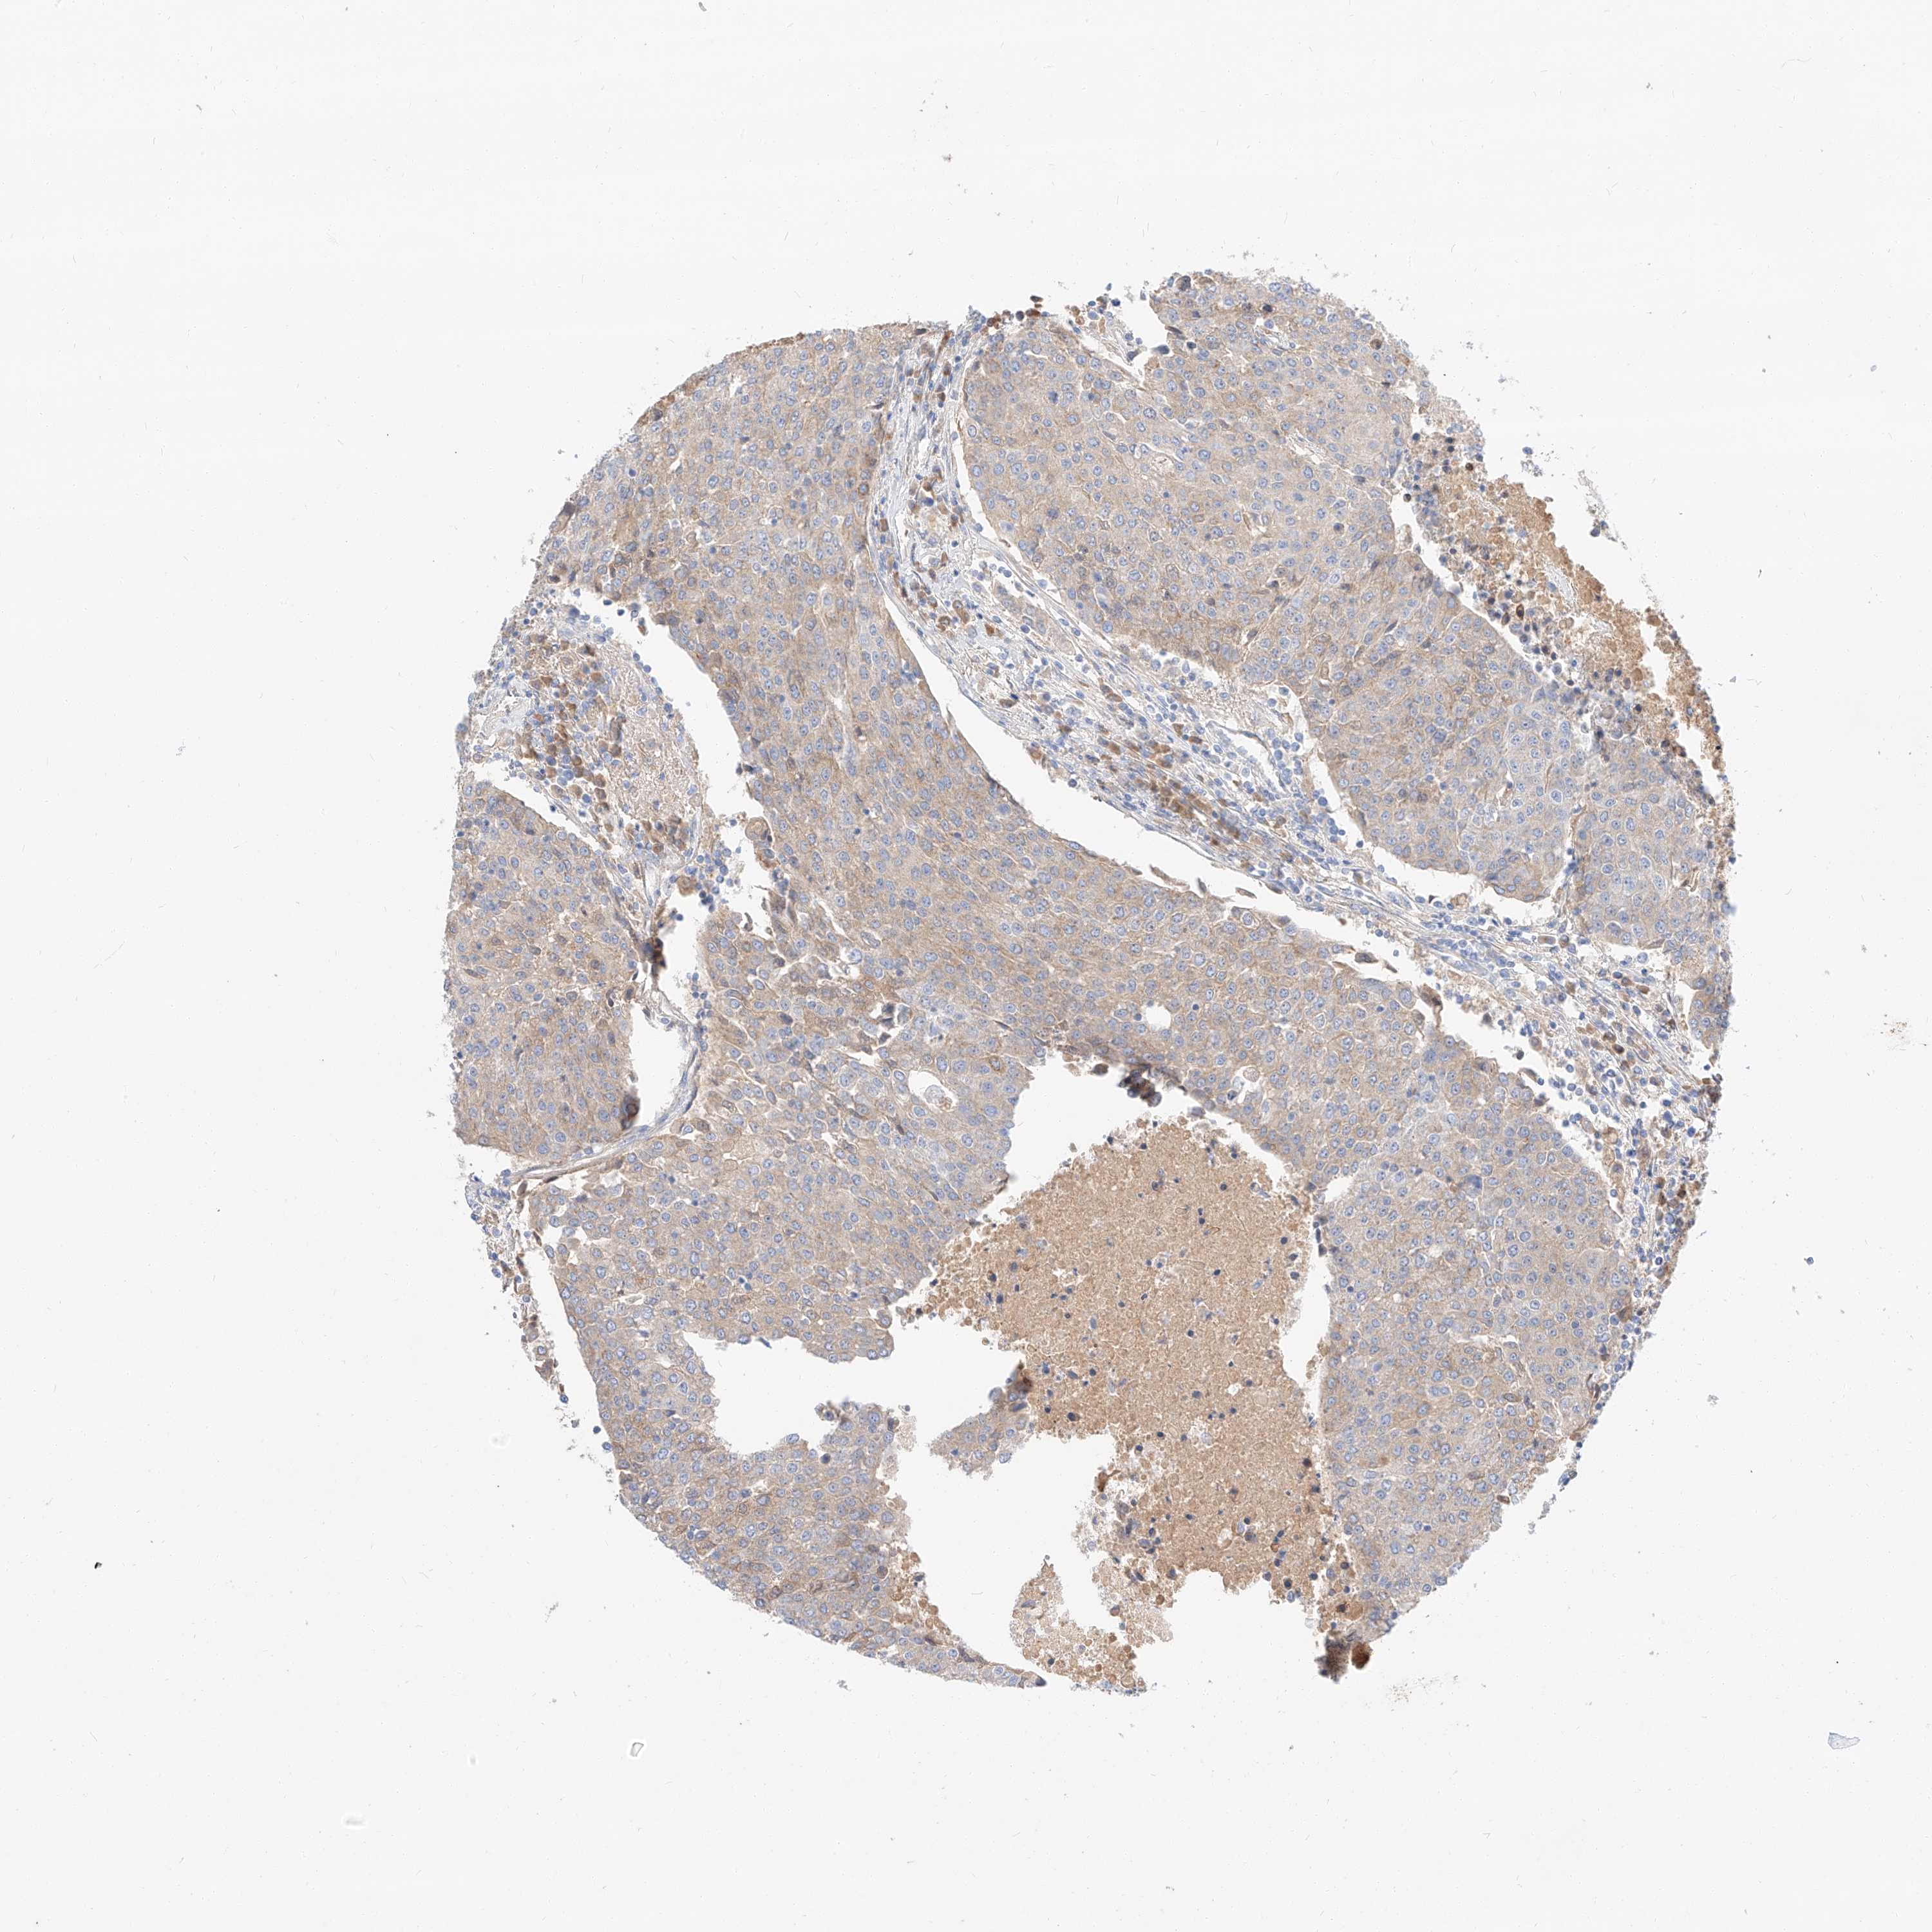

UROTHELIAL CANCER - Protein expressioni

A mouse-over function shows sample information and annotation data. Click on an image to view it in a full screen mode. Samples can be filtered based on level of antibody staining by selecting one or several of the following categories: high, medium, low and not detected. The assay and annotation is described here.

Note that samples used for immunohistochemistry by the Human Protein Atlas do not correspond to samples in the TCGA dataset.

Antibody stainingi

Antibody staining in the annotated cell types in the current human tissue is reported as not detected, low, medium, or high, based on conventional immunohistochemistry profiling in selected tissues. This score is based on the combination of the staining intensity and fraction of stained cells.

Each image is clickable and will lead to virtual microscopy that enables deeper exploration of all samples and also displays staining intensity scores, fraction scores and subcellular localization as well as patient and tissue information for each sample.

Antibody HPA029712

Antibody HPA029713

Staining

High

Medium

Low

Not detected

Intensity

Strong

Moderate

Weak

Negative

Quantity

>75%

75%-25%

<25%

None

Location

Nuclear

Cytoplasmic/membranous

Cytoplasmic/membranous,nuclear

Urothelial carcinoma, Low grade